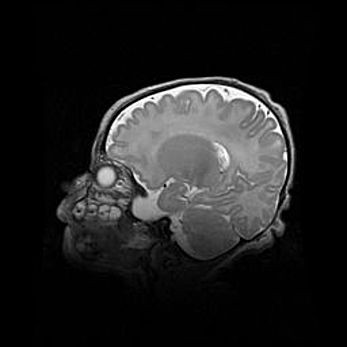

Мальформация Денди-Уокера. Киста задней черепной ямки.

Агенезия мозолистого тела.

Возраст: 2,5 месяца

Вес: 2420 г

Пол: женский

Окружность головы: 37 см

Срок гестации: 32 недели

Мальформация Денди—Уокера — редкий вид патологии ЦНС, представляющий собой врожденный порок развития каудального отдела ствола и червя мозжечка, ведущий к неполному раскрытию срединной (Мажанди) и латеральных (Лушка) апертур IV желудочка мозга. Для этогно синдрома характерна триада симптомов: гипотрофия червя мозжечка и/или полушарий мозжечка, кисты задней черепной ямки, гидроцефалия различной степени. В 70% случаев порок сочетается и с другими аномалиями головного мозга, в частности с агенезией мозолистого тела.